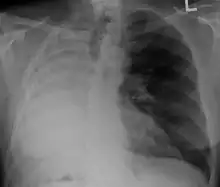

Anatomical changes

After a pneumonectomy is performed, changes in the thoracic cavity occur to compensate for the altered anatomy. The remaining lung hyperinflates as well as shifting over along with the heart towards the now empty space. This space is full of air initially after surgery, but then it is absorbed, and fluid eventually takes its place.[9] The fluid which fills the residual space in the chest cavity slowly gelatinizes into a proteinaceous material, and the chest scaffold collapses slightly.